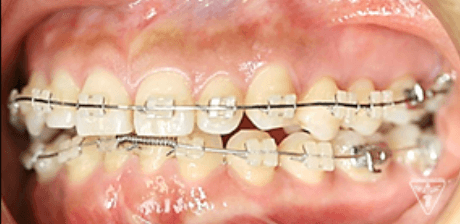

治療過程③